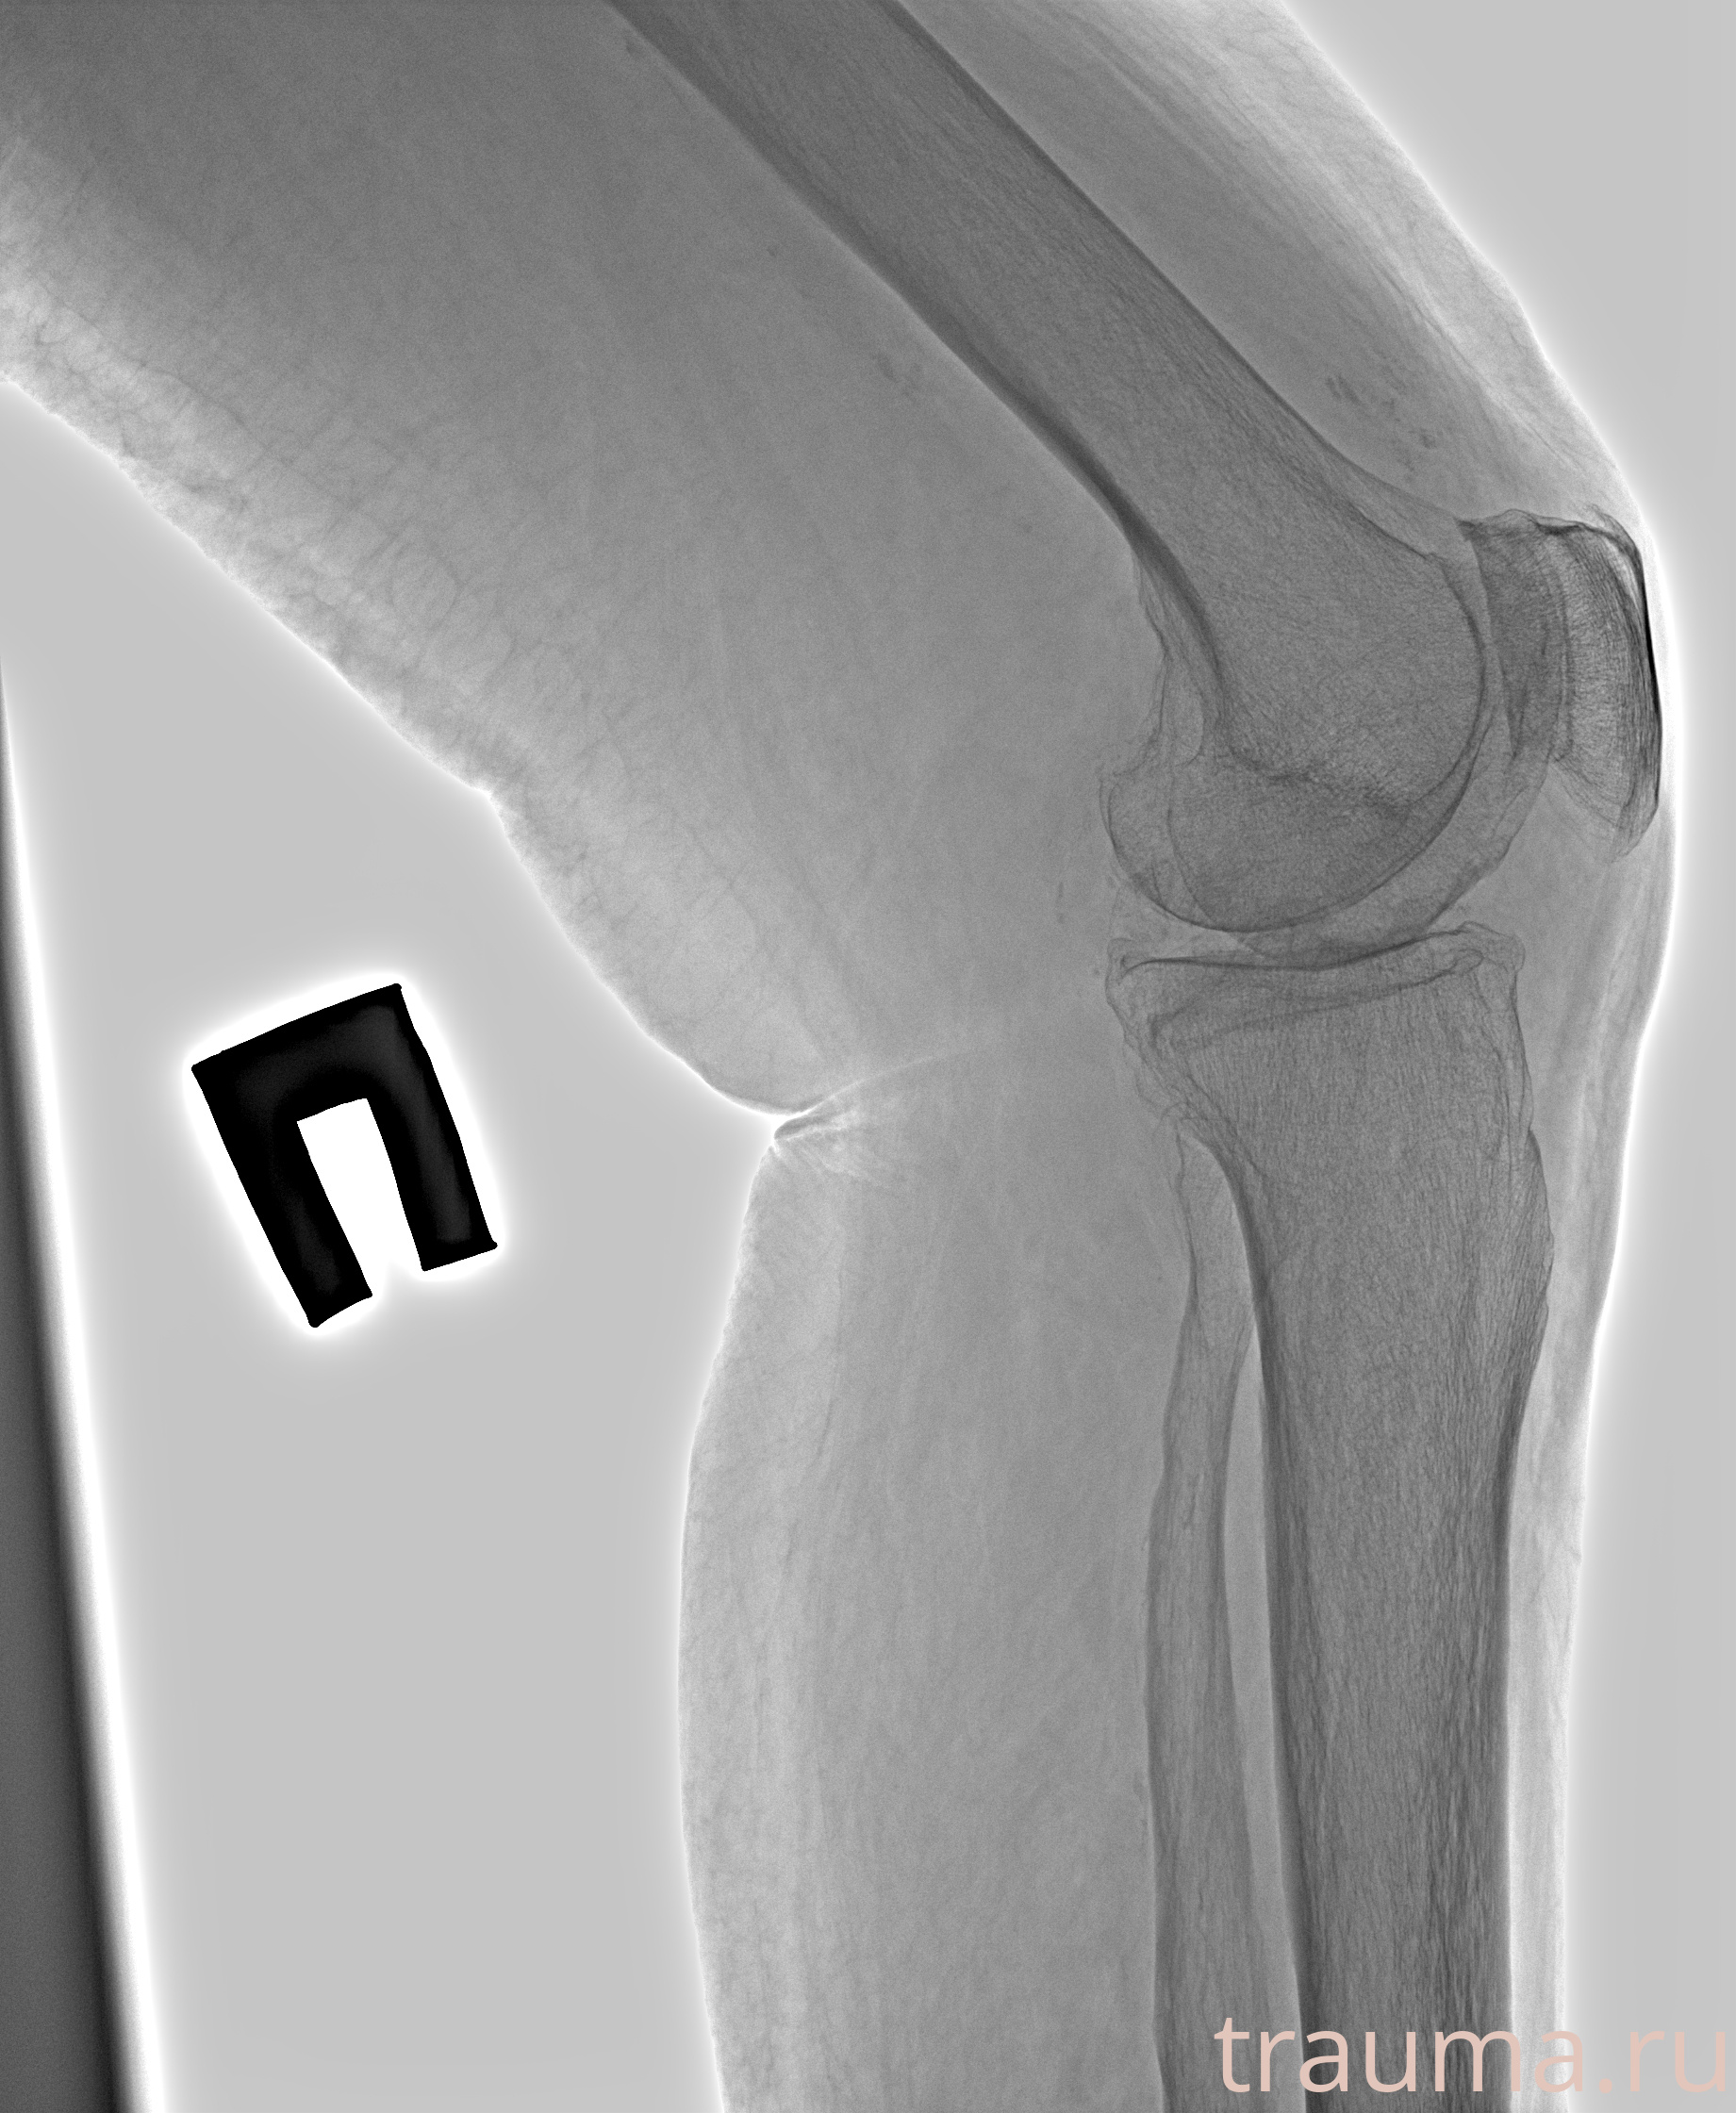

Рентгенограммы

Рентген на дому: по вашему адресу приезжает врач-рентгенолог, травматолог-ортопед с мобильным рентгеновским аппаратом, проводит диагностику травмы или заболевания, делает необходимые рентгенограммы, дает рекомендации по дальнейшему лечению. Получить качественные снимки в домашних условиях возможно благодаря уникальной методике, разработанной МосРентген Центром для института  Склифосовского